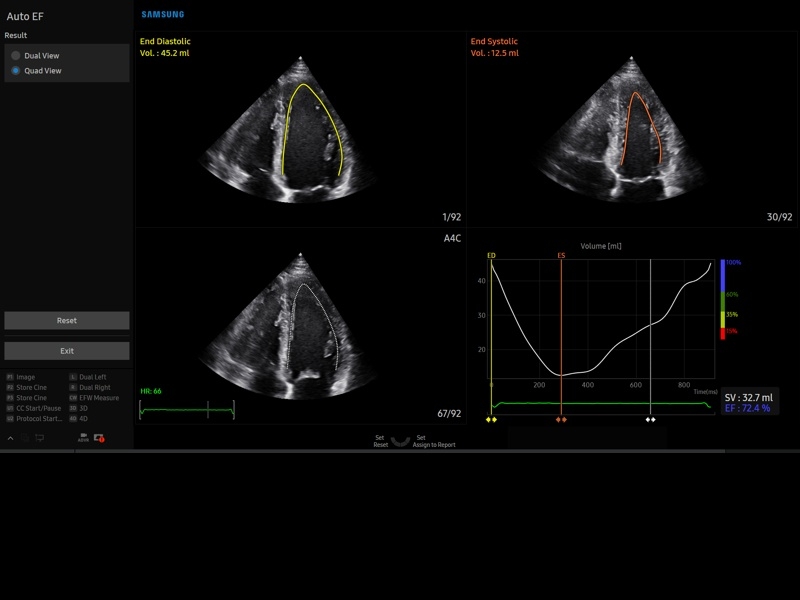

• Пакет кардиологических исследований.

М-режим:измерение диаметра аорты, передне-заднего размера ЛП, толщины МЖП (систолическая и диастолическая), толщины ЗСЛЖ (систолическая и диастолическая), размеров ЛЖ и ПЖ (систолический и диастолический), ФВ (Teichholz).

B-режим:измерение диаметра аорты (восходящей, дуги, нисходящей, на уровне синусов Вальсальвы, на уровне створок аортального клапана), определение размеров ЛП и ПП (максимальный, минимальный, систолический, диастолический, переднее-задний, верхнее-нижний, медиально-латеральный), расчет объемов ЛП и ПП, объемов ЛЖ (метод "Площадь-Длина", метод дисков (Simpson)), массы миокарда ЛЖ, индекса массы миокарда ЛЖ.

• МодульStrain+- программа не векторной оценки степени сократимости миокарда с выведением автоматически расчетов и графиков на экране отдельно по каждому сегменту.